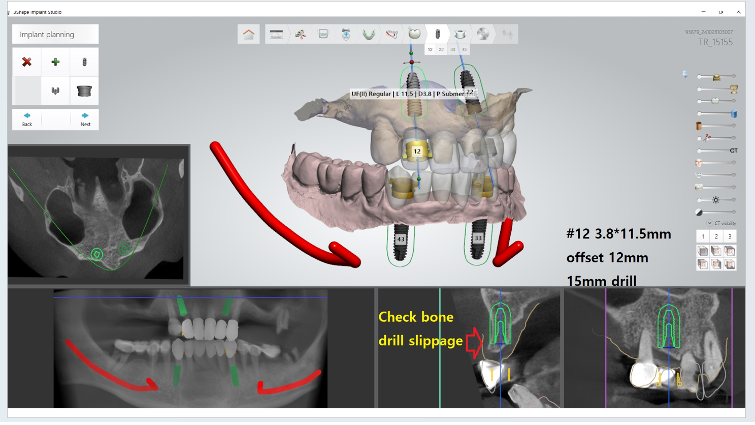

Yüksek riskli vakalarda cerrahi süreyi kısaltmak ve doku travmasını minimumda tutmak hayati önem taşır. Bu nedenle, tamamen Guided (Rehberli) Cerrahi yolunu seçtim. Dijital planlama sayesinde, milimetrik hassasiyetle çalışarak enfeksiyon riskini ve operasyon sonrası ödemi minimize etmeyi hedefledim. Kesik yok, dikiş yok, enfeksiyon riski az.

Bu vakada, implant yüzeyinin kemikle olan biyolojik etkileşimini en üst seviyeye çıkarmak için UV Active (fotofonksiyonel) implantlar kullandım. UV ışını ile aktive edilen bu implant yüzeyleri, diyabet gibi iyileşmenin yavaş olduğu durumlarda kemik hücrelerinin implanta çok daha hızlı ve güçlü tutunmasını sağlar. Alt ve üst çeneye rehberli cerrahiyle yerleştirdiğim bu implantları, Locator tutucularla destekleyerek hastamız için hem güvenli hem de yeterince stabil bir hareketli protez altyapısı kurdum. Hastayı yaklaşık 5 yıldır takip ediyorum, herhangi bir problemi olmadan dişlerini sağlıkla kullanıyor.

Klinik Not: Hekimlikte başarı, hastanın sistemik risklerine uygun teknolojiyi doğru yerde kullanmaktır. HbA1c seviyesi 10 olan bu vakada; dijital planlamanın (Guided) getirdiği cerrahi doğruluk ile UV Active teknolojisinin sunduğu biyolojik hızı birleştirdim. Sonuç; diyabetik risklerin başarıyla yönetildiği, konforlu bir iyileşme süreci ve hastamızın yaşam kalitesine geri kazandırılan bir fonksiyon oldu.